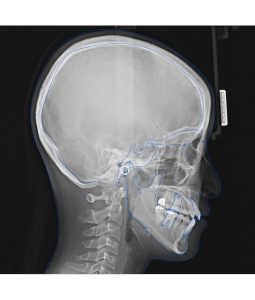

もう一つのレントゲンは、横顔を撮影する機械です。

頭を軽く固定した後、

こちらの機械も動くので真っ直ぐ正面を見てお待ちください。

このような横顔が撮れます。